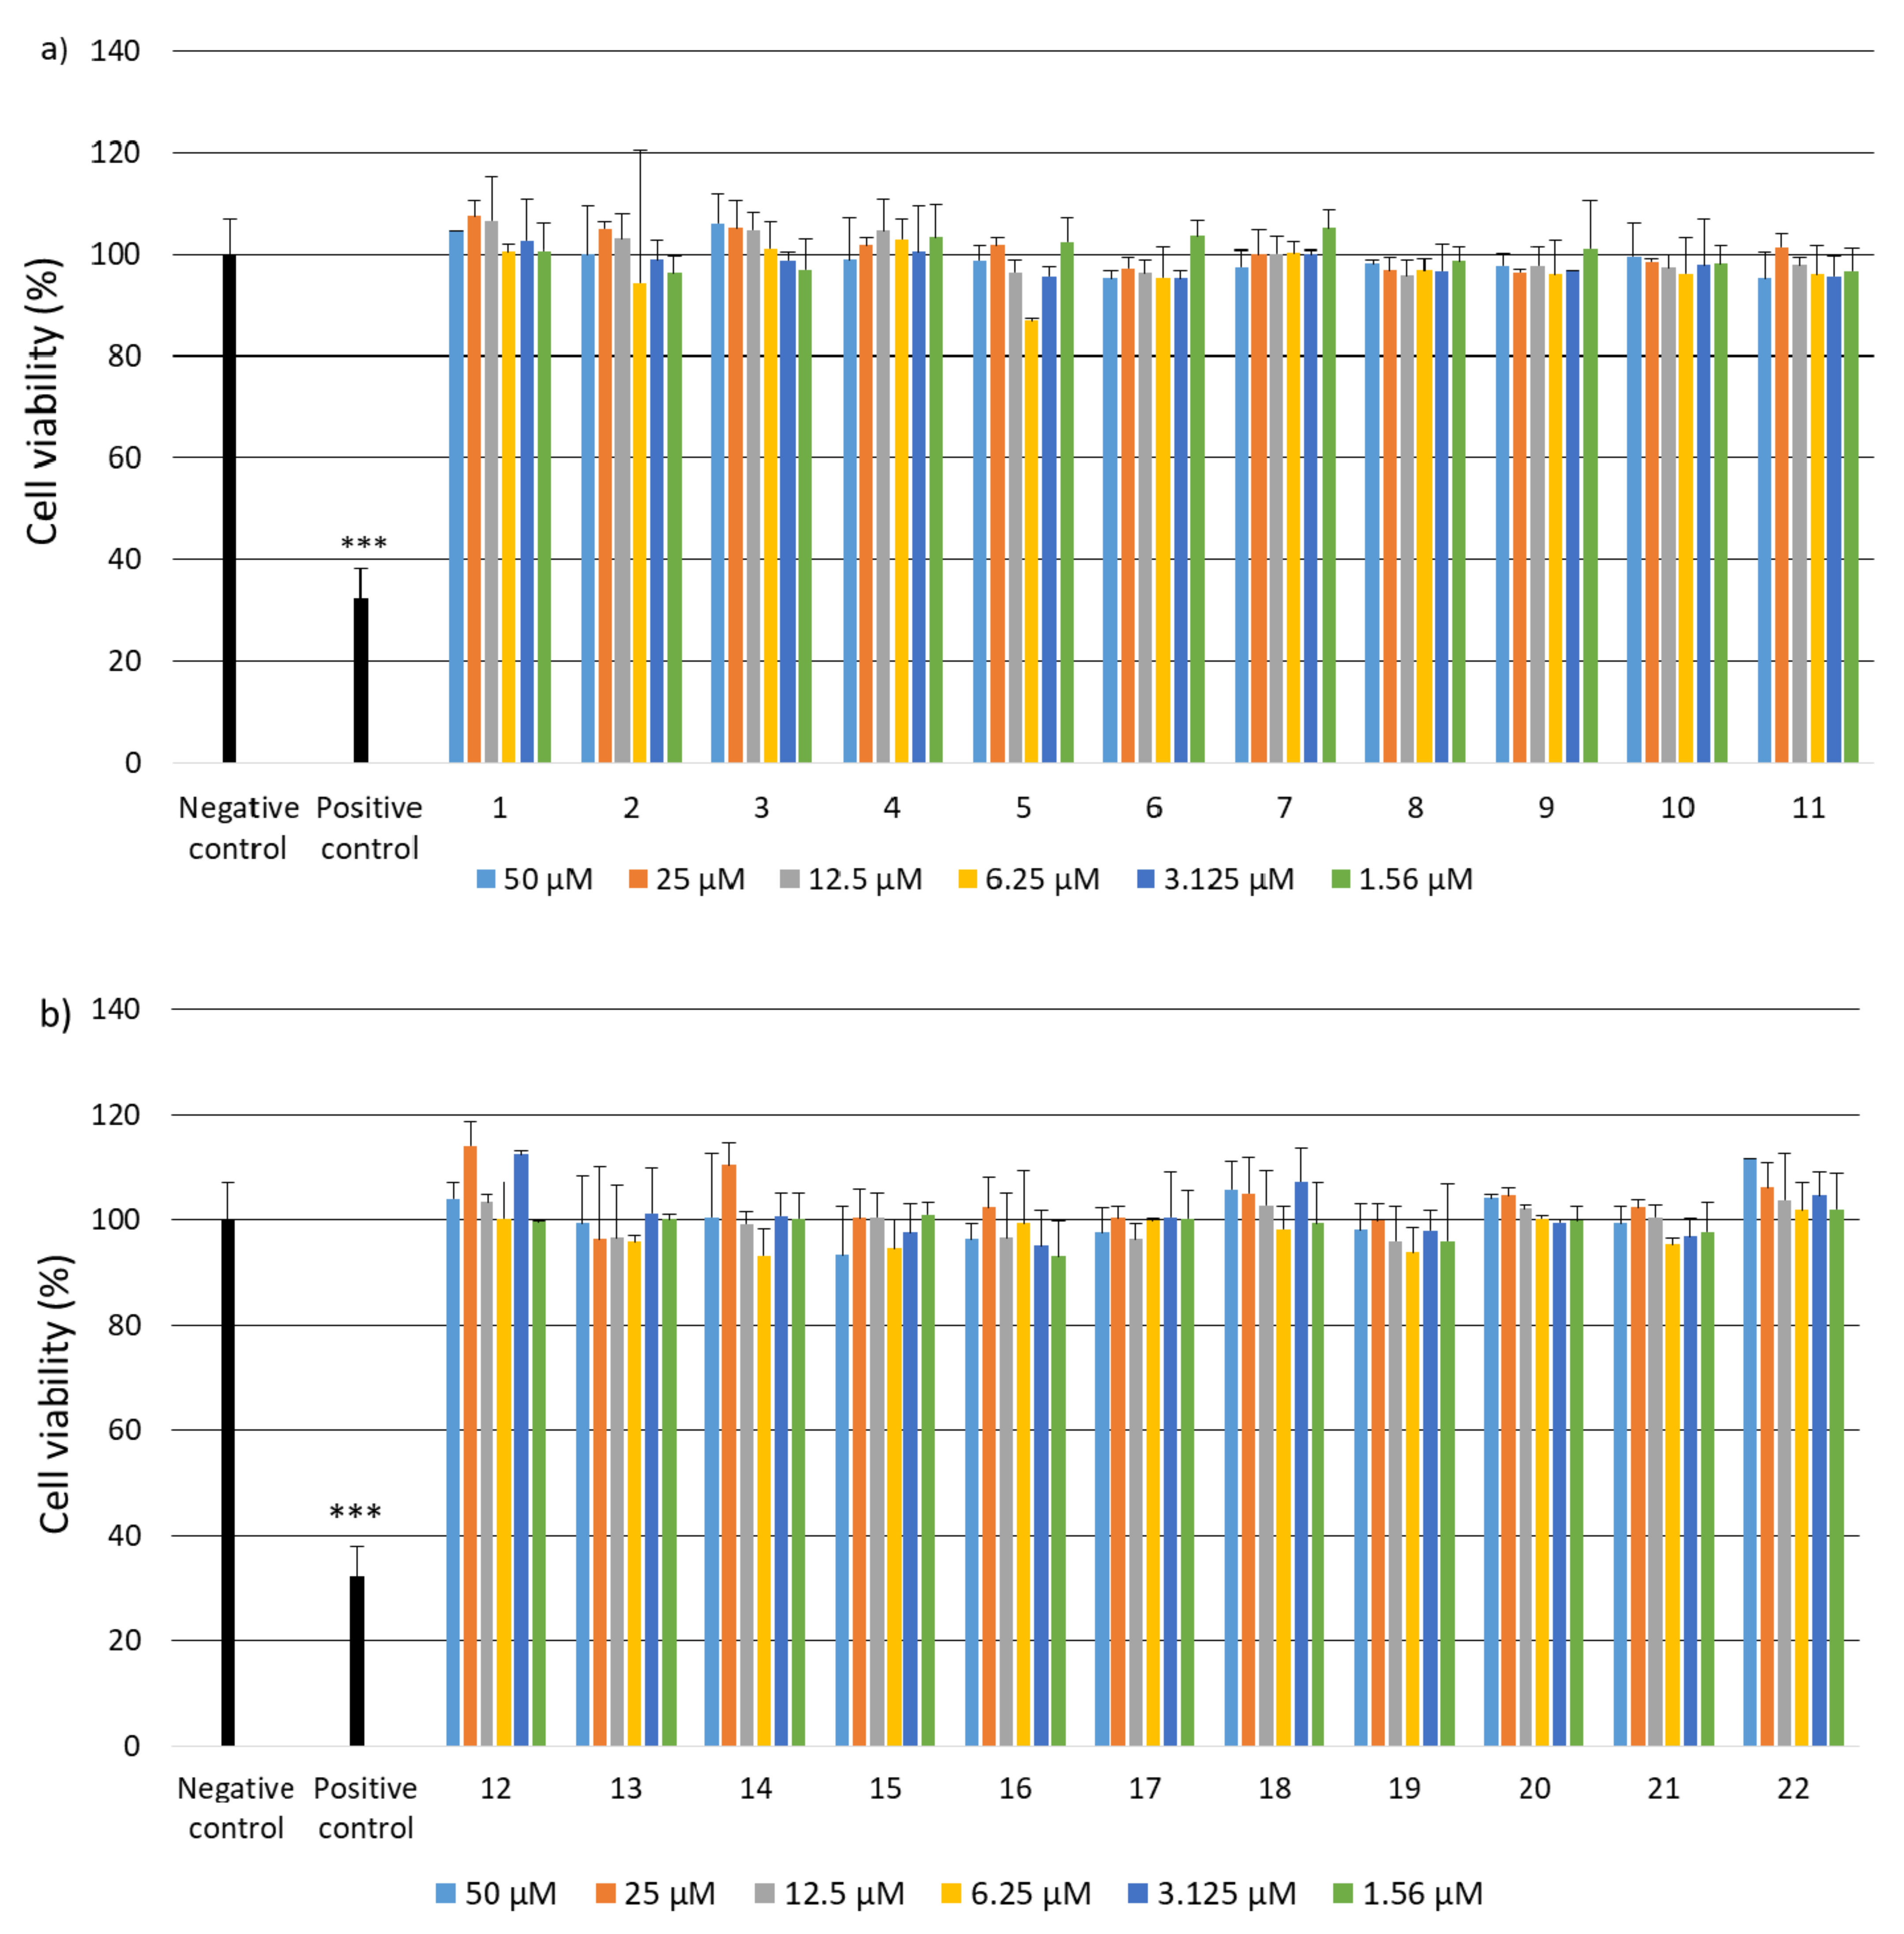

2.2. Research on Biological Activity of Collagen IV Fragments

3.7. Biological Activity Studies

- Cell Viability